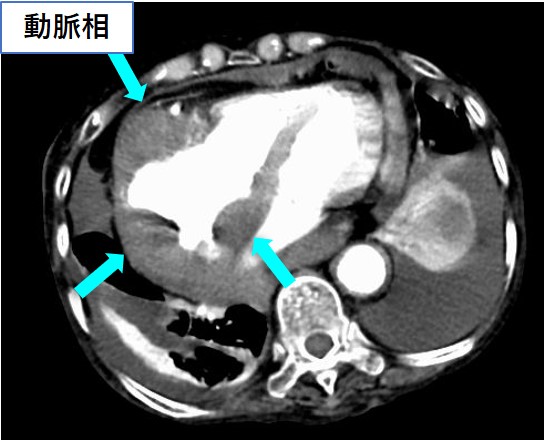

腹部造影CT(平衡相)

両側腎盂に壁肥厚を認める。

<後腹膜病変>

• 水腎症・尿管拡張(33%)

• Hairy kidney(68%)